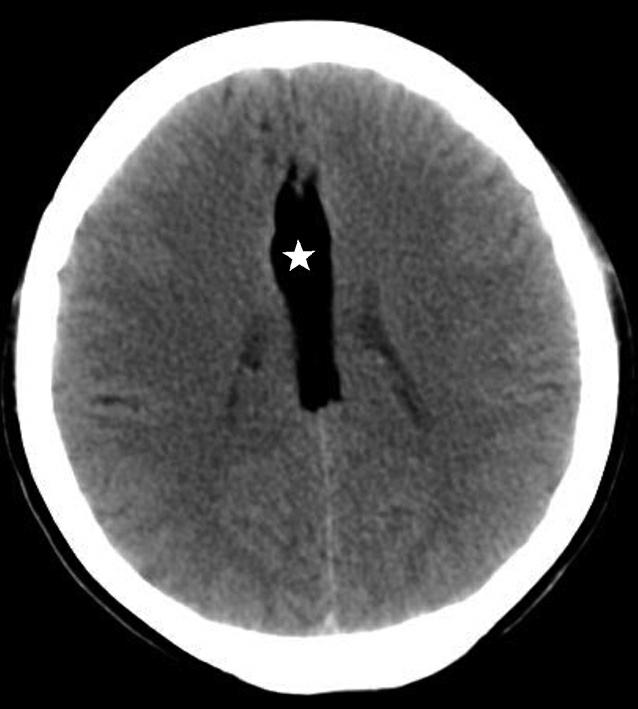

Alberta卒中项目早期CT评分(Alberta stroke program early CT score,ASPECTS)是一种评价急性缺血性卒中患者大脑中动脉供血区早期缺血性改变的简单、可靠、系统化的方法,是常用的脑卒中评定量表之一,可对缺血性病变快速进行半定量评价,有助于判定溶栓效果和远期预后。该评分主要基于CT平扫,具体分区如下(图1-2-76)所示,即选取大脑中动脉供血区2个层面。分区后共10个区域,每个区域记1分。评分时任何区域只要有低密度灶,则扣除该区域得分。正常脑ASPECTS评分为满分(10分),若MCA供血区广泛梗死累及全部区域时,则ASPECTS评分为0分。

图1-2-76 ASPECTS评分脑组织分区

A.在基底节层面(即丘脑和纹状体平面),分为各级分支M 1 、M 2 、M 3 、岛叶(缩写I)、豆状核(缩写L)、尾状核(缩写C)和内囊(缩写IC)后肢等7个区域;B.在基底节以上层面(基底节层面上2cm),包括M 4 、M 5 和M 6 。